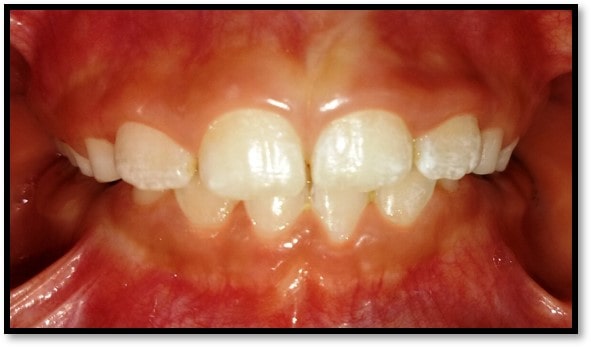

We at the Department of Pediatric & Preventive Dentistry focus on comprehensive oral health care needs of a child from infancy to adulthood and provide comprehensive, therapeutic as well as preventive care to all children including those with special care needs.

Treatment and Services